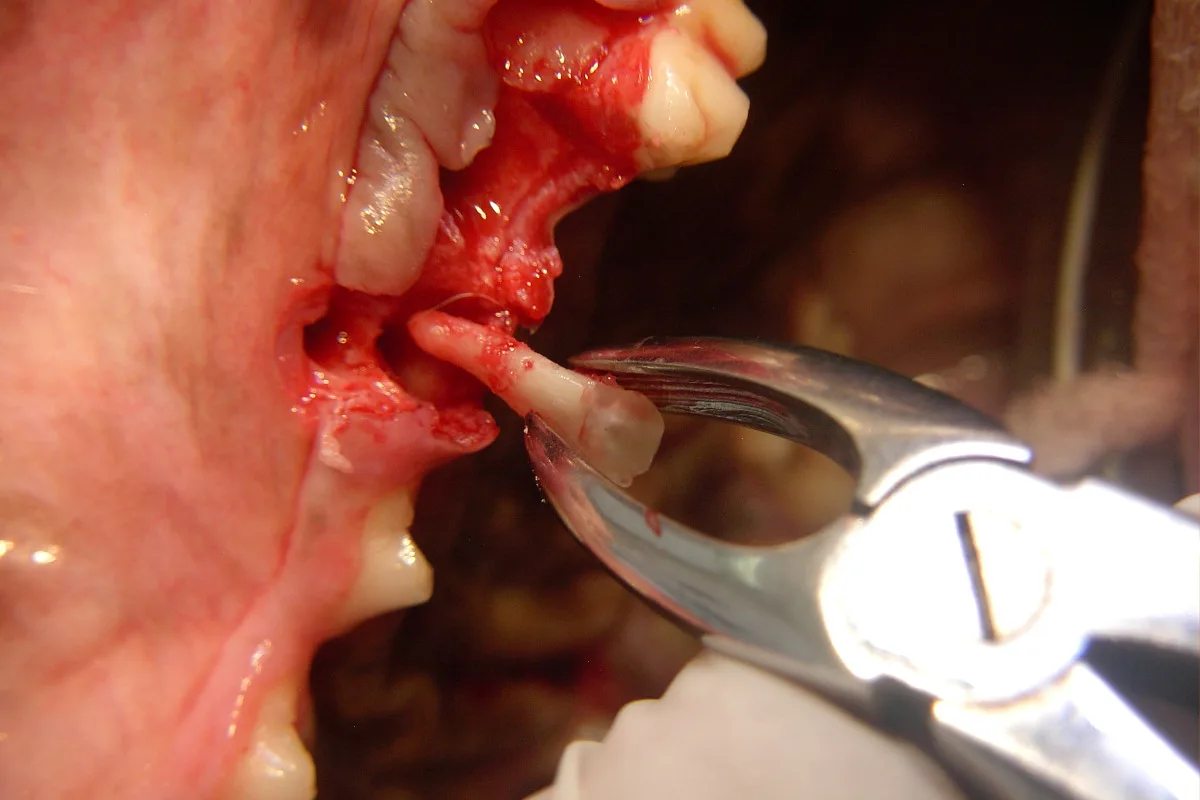

Step 7

At this point, the distal root segment is grasped with small extraction forceps and gentle rotational force is applied while extracting the root. Once out, the root should be inspected to make sure it has been removed completely; typically the root apex will be round. Postoperative dental radiographs also help identify any retained root tips.